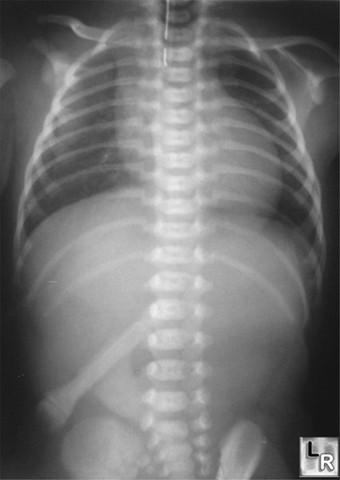

اینم عکس بعدی ....این نوزاد چه اختلال عمده و تهدید کننده حیاتی داره؟راهنما:مسیر لوله NGT رو دنبال کنید.

سلام سروش جان...ممنون از همراهیت....اون شکل شبیه آچار بازو و آرنج کسیه که اونو گرفته تا ازش عکس رو بگیرن...مورد نظر من اون نیست... NGT هم لوله ایه که از راه بینی می فرستن پایین تا به معده بیمار برسه برای تغذیه بیمار یا برای خالی کردن معده بیمار...خوب؟ ولی فقط برای بیمارانی که نیاز داشته باشن...اون خط سفید رنگی که از بالای عکس تا حدودا پشت قلب کشیده شده لوله NG هستش ولی باید تا معده می رسیده....راهنمایی برای بقیه دوستان هم شد...در مورد نوزاد بودنش شک دارم شاید عکس را بزرگتر کرده باشن...شایدم دیرتر هم به بیماریش پی بردن ولی معمولا در هفته اول زندگی تشخیص داده میشه.

سلام دوستان......ضمن تشکر به خاطر همراهیتون...به نظر می رسه جناب دکتر "dr-health" سرشون شلوغه و پاسخی ارسال نکردن. ازشون درخواست می کنم نظرشون درباره سایز "نوزاد" و "شکل شبه آچار" در شکم این گرافی ارسال کنند....اما پاسخ با دقت در مسیر لوله NG متوجه میشین که این لوله به معده نرسیده در نتیجه میشه بیماری اون رو تشخیص داد" بسته بودن مری" یا به قول ما دکترا "آترزی مری"........البته گرافی یه نکته جالب دیگه هم داره و اون نبود حباب گاز در معده و روده های نوزاده!! که دلیلش هم همون بسته بودن مری است.